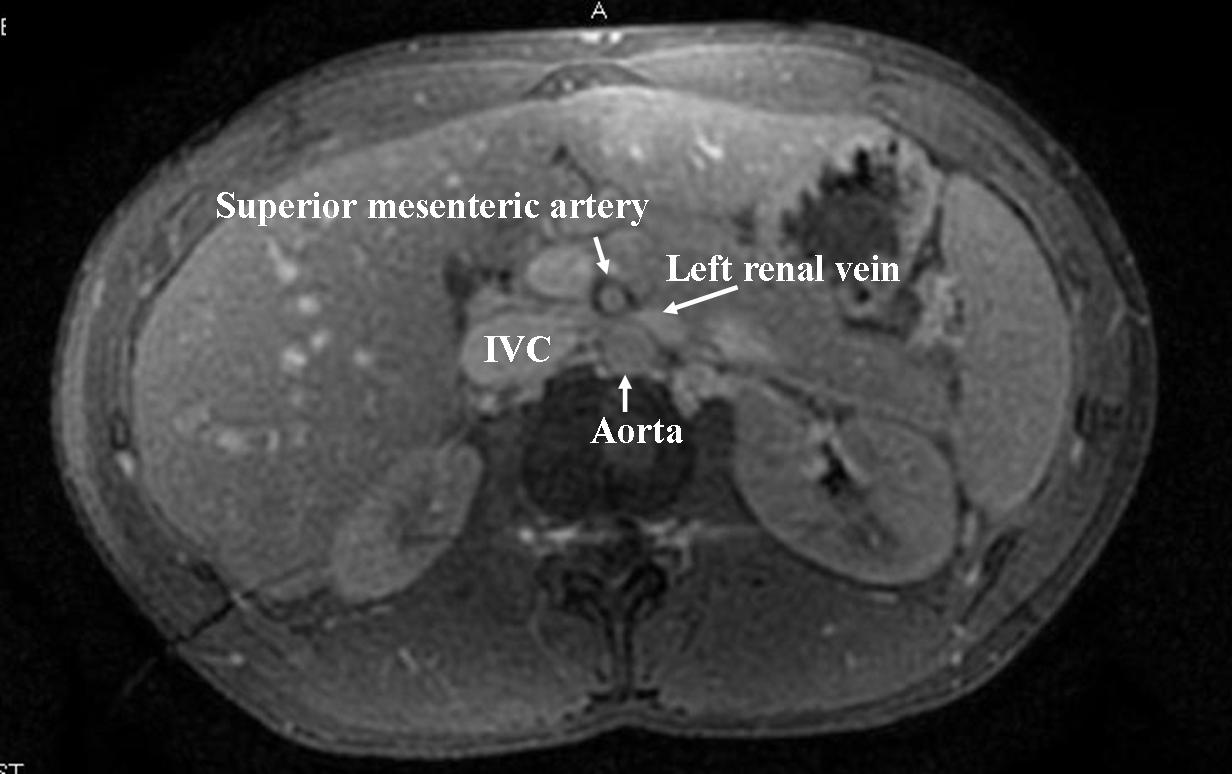

The diagnosis of nutcracker syndrome is often made with abdominal imaging. The typical finding is a left renal vein compressed between the aorta and the superior mesenteric artery. Other findings will be dilatation of the hilar portion of the left renal vein, dilatation of the left gonadal vein and abdominal varices. Ultrasound is often the first study to be utilized. As the flow limitations vary with patient position, it is important to document the position in which the study was performed. Also, it is useful to document flow in multiple positions. Nonetheless, computed tomography is the most commonly utilized technique. MRI can also offer great images as can be seen in the following image: